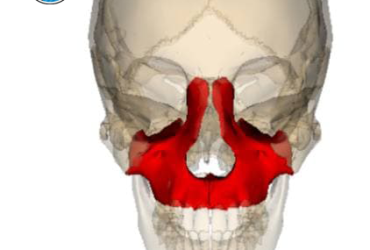

شکستگی ماگزیلا

شکستگی ماگزیلا (فک بالا) | علائم، علل و روشهای درمان مقدمه شکستگی ماگزیلا (Maxillary Fracture)…